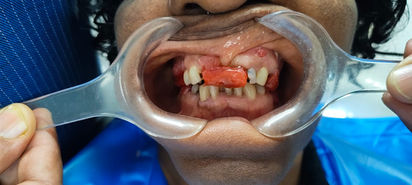

Un implant dentaire est la solution la plus moderne et durable pour remplacer une dent manquante. Il s'agit d'une racine artificielle en titane placée dans l'os, sur laquelle on fixe une dent définitive en céramique. Le résultat est identique à une dent naturelle, tant par l'esthétique que par le confort pour manger et parler.

Une preuve de notre expertise : Voici un exemple concret d'une restauration complète réalisée récemment. Ce patient a reçu 11 implants dentaires au total, retrouvant une dentition parfaite et fonctionnelle à un prix incroyable, bien inférieur aux tarifs pratiqués en Europe ou en Amérique.